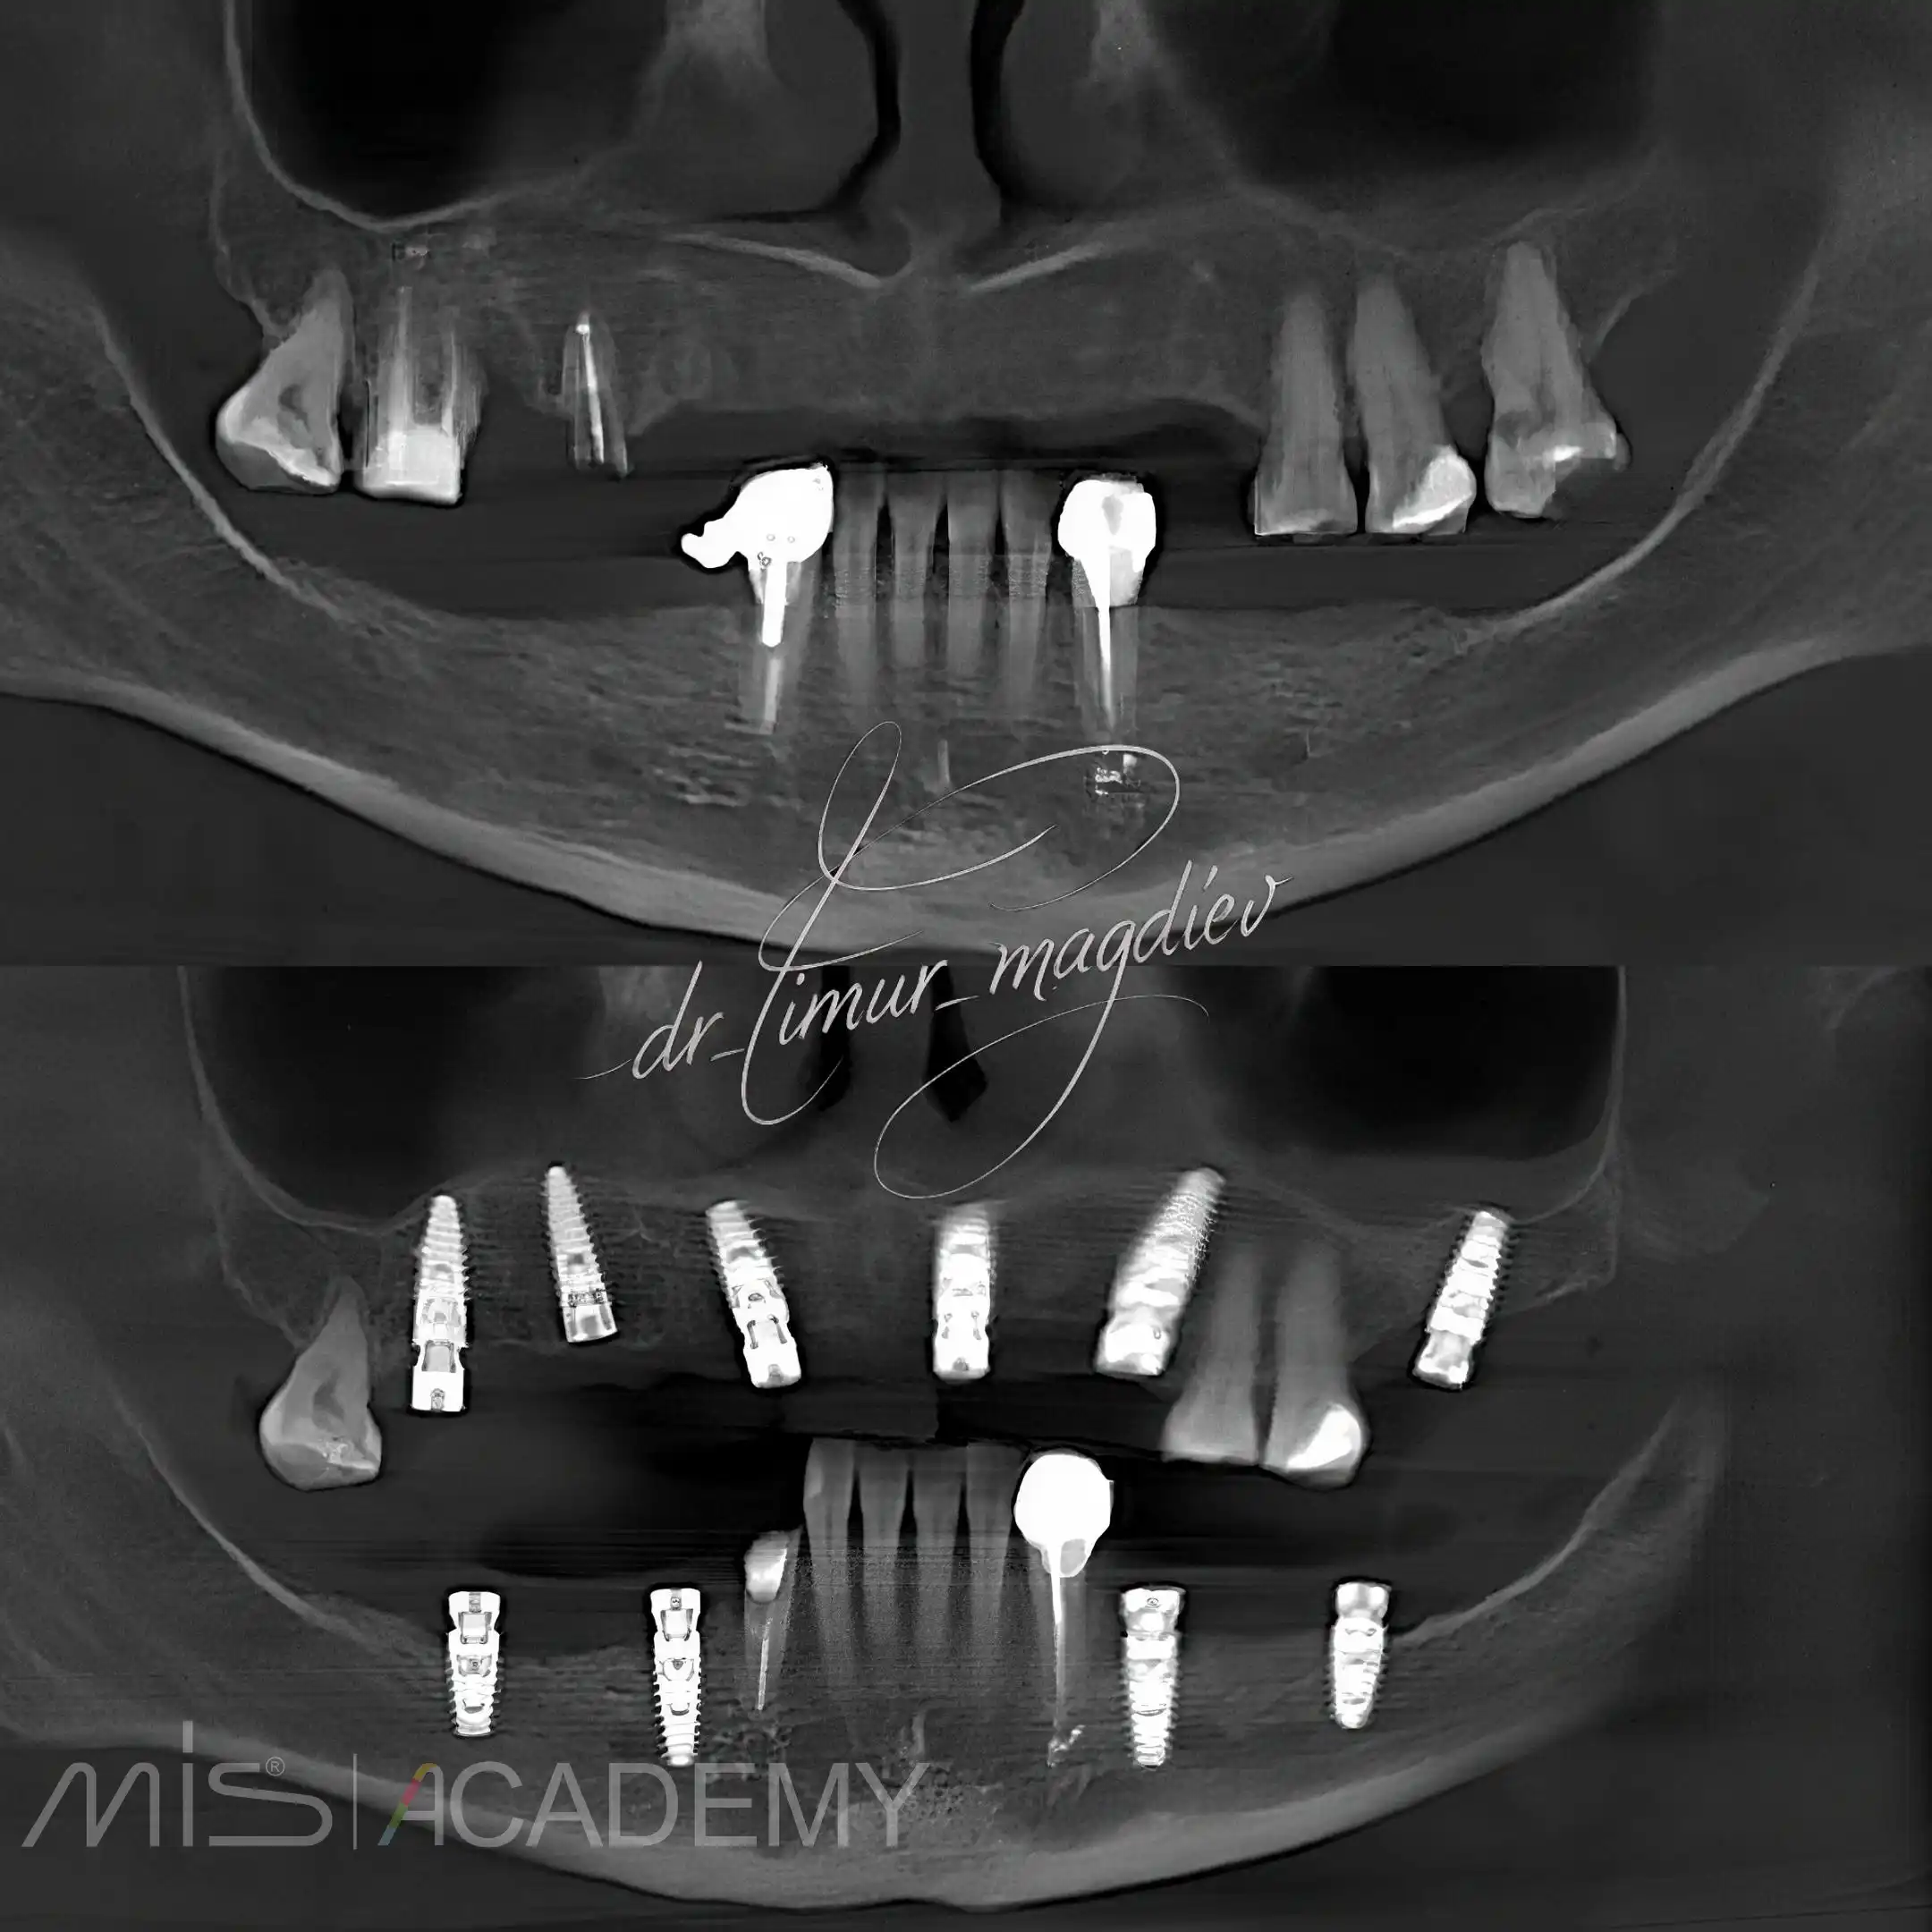

Комплексная реабилитация пациента; в полном навигационном протоколе:

— Установлены имплантаты MIS C1 + Connect абатменты.

— Установлены циркониевые мостовидные протезы с опорой на имплантаты.